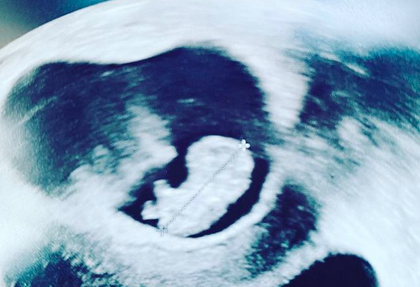

A tavaly augusztusban élete legnagyobb tragédiáját átélő L.L. Junior és új párja, Körtvélyessy Kinga szülői örömök elé néz.